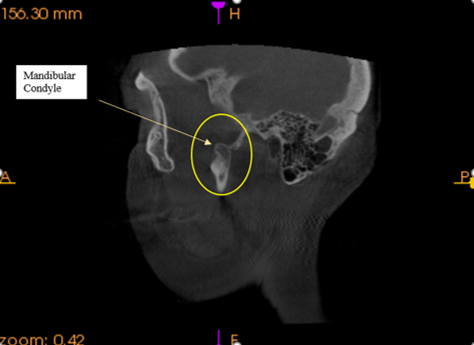

Left side view. Oral surgeon said I was lucky I did not break off the mandibular condyle.